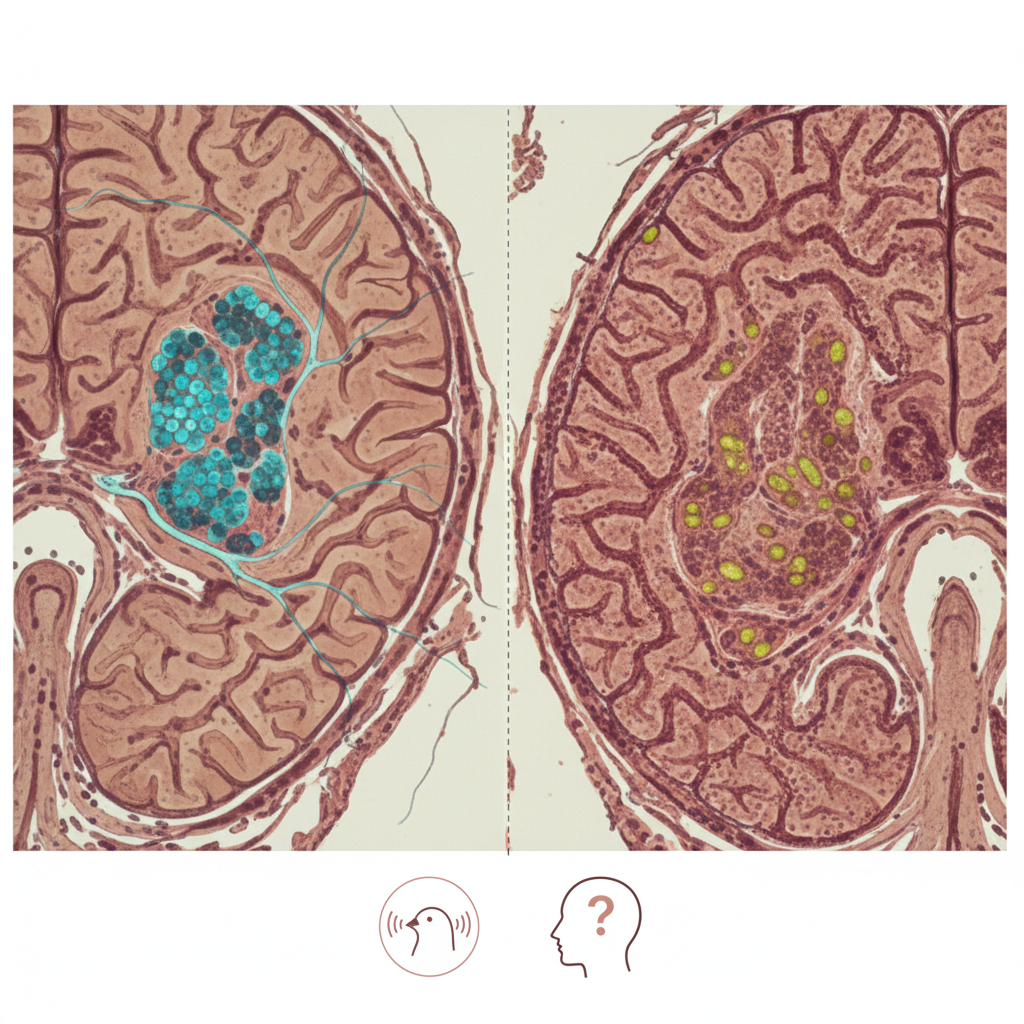

La inflamación crónica podría dejar huellas duraderas en células madre del intestino y ayudar a explicar un mayor riesgo de cáncer colorrectal, pero la evidencia disponible aquí no basta para confirmarlo

La inflamación crónica podría dejar huellas duraderas en células madre del intestino y ayudar a explicar un mayor riesgo de cáncer colorrectal, pero la evidencia disponible aquí no basta para confirmarlo Pocas ideas son tan importantes en la biología...